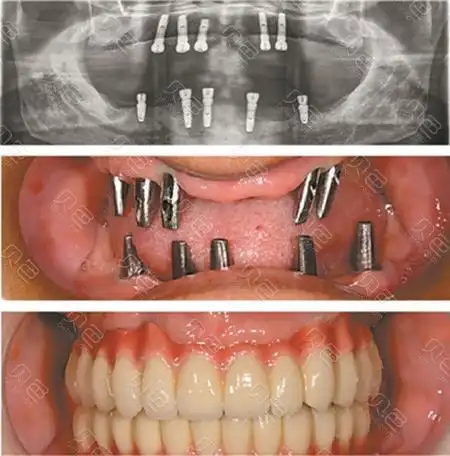

满嘴全部种牙我一想就很害怕,你们种牙疼不疼? - 贝色口腔